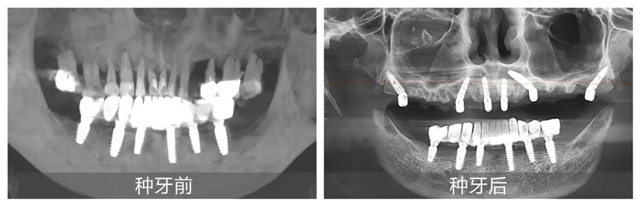

在配備數(shù)字化導(dǎo)板系統(tǒng)的現(xiàn)代化手術(shù)室里,黃杰終于迎來期盼已久的“試煉場(chǎng)”。短短一年,就已經(jīng)成功種植修復(fù)2100+顆牙,完成無牙頜即刻負(fù)重手術(shù)110臺(tái)。不僅在種牙數(shù)量上取得了突破,在質(zhì)量方面也同樣出色。